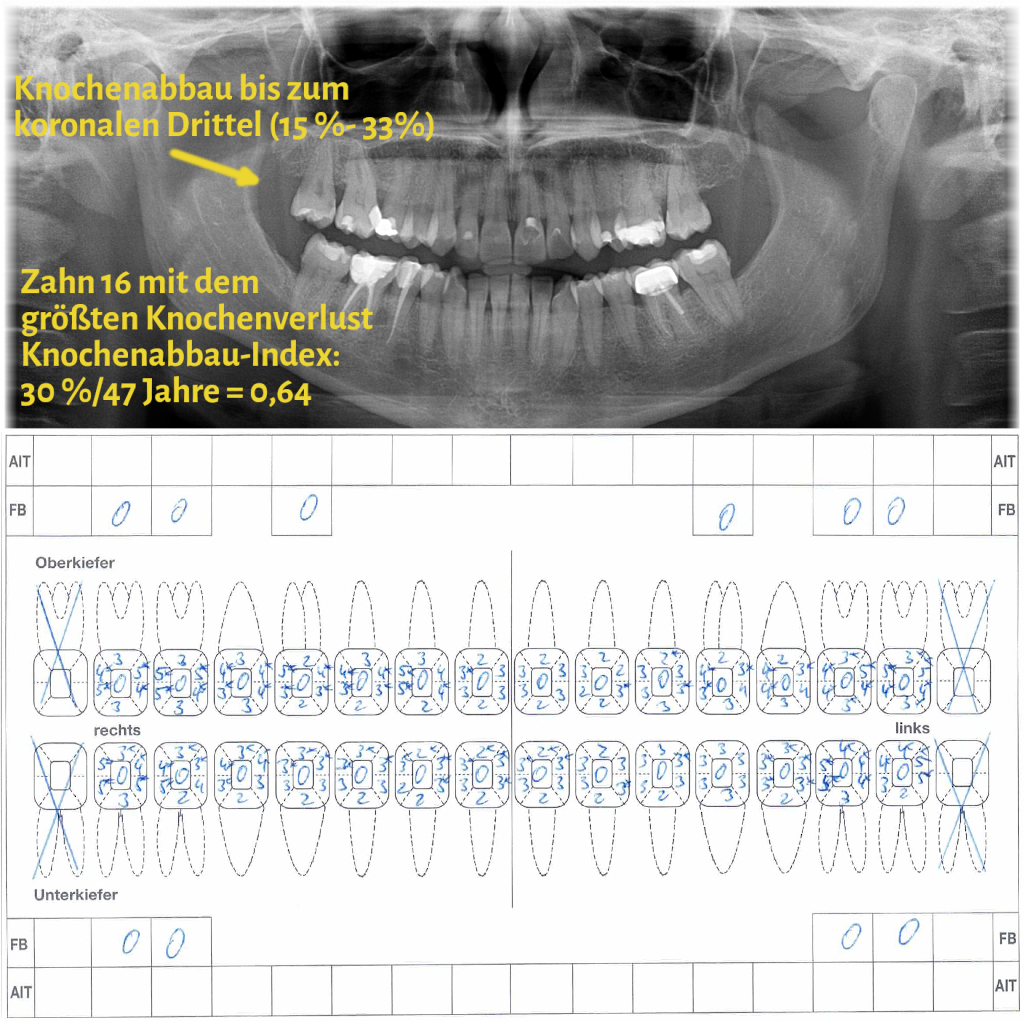

Der Grad enthält Informationen zur Progressionsrate der Erkrankung und dem Vorliegen von patientenspezifischen Risikofaktoren (Nikotinkonsum und Diabetes/HbA1c). Die Progressionsrate kann direkt anhand von Vorbefunden abgeschätzt werden oder indirekt durch den sogenannten Knochenabbauindex (KA %/Alter). Dabei wird der Zahn auf dem Röntgenbild berücksichtigt, der den stärksten marginalen Knochenabbau hat. Das Vorliegen von Risikofaktoren kann zu einem Upgrade führen. Fehlen diese Risikofaktoren, führt das aber nicht zu einem Downgrade.